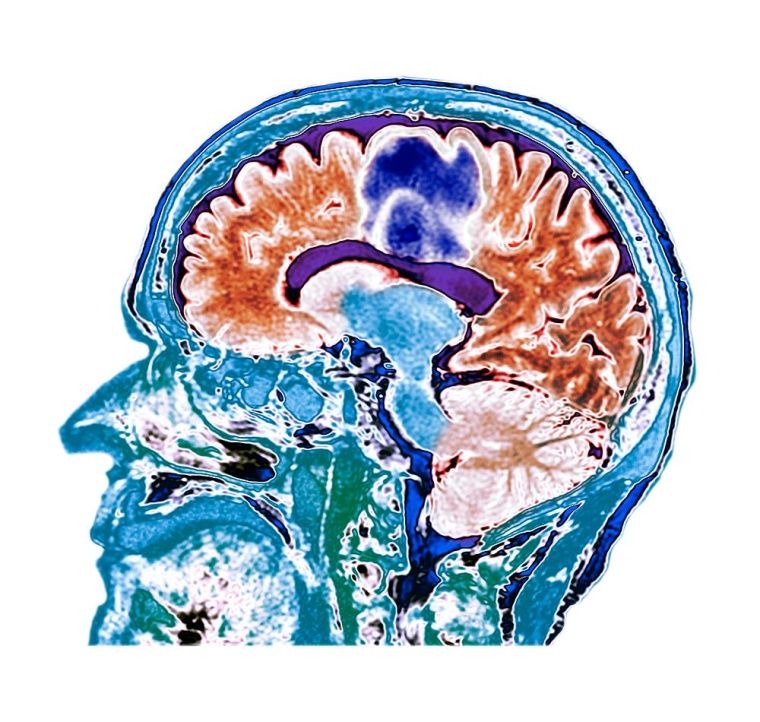

Radioimmuntherapie von Kopf-Hals-Tumoren

Bei der Behandlung verschiedener Krebsarten, so auch im Kopf-Hals-Bereich, ist heute die Immuntherapie mit Checkpoint-Inhibitoren zusätzlich zu Bestrahlung und Chemotherapie üblich – doch ist Letztere immer nötig?